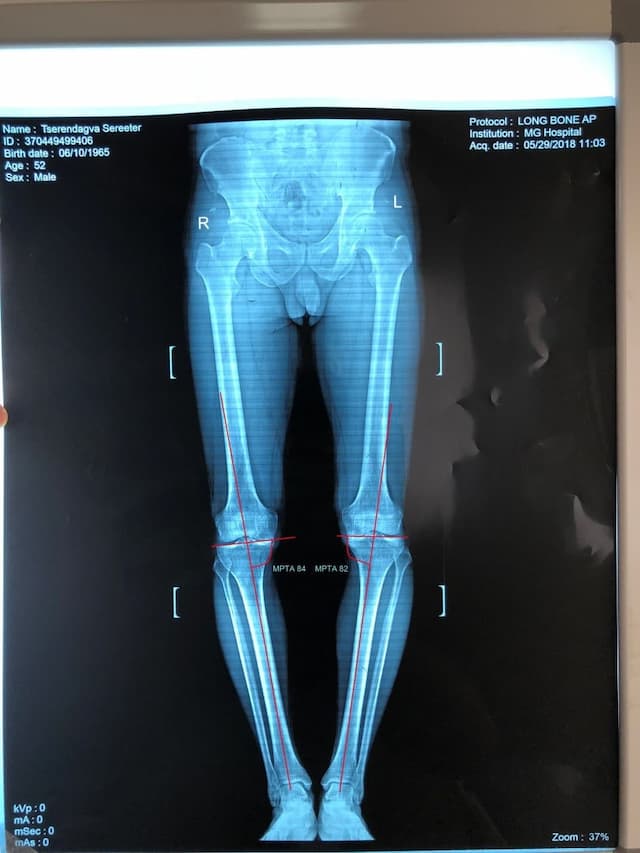

Эмчлүүлэгчийн өвчний явц, үе шат, өвдөгний үений өвдөлтийн хэлбэр, хөдөлгөөний далайц зэргийг сайтар нягталсны үндсэн дээр мэс заслаар биеийн жингийн шугам, шаантны дотор дээд өнцөг, ясны хугарлын цэг, тэлэгдэх өнцгийг нарийн тохируулснаар хүссэн үр дүндээ хүрэх боломжтой.

Шаантны дотор дээд өнцөг мэс заслын өмнө баруун хөлд 84o, зүүн хөлд 82o байсан бол мэс заслын дар аа баруун хөлд 96o, зүүн хөлд 94o болж засагдсан байдал.